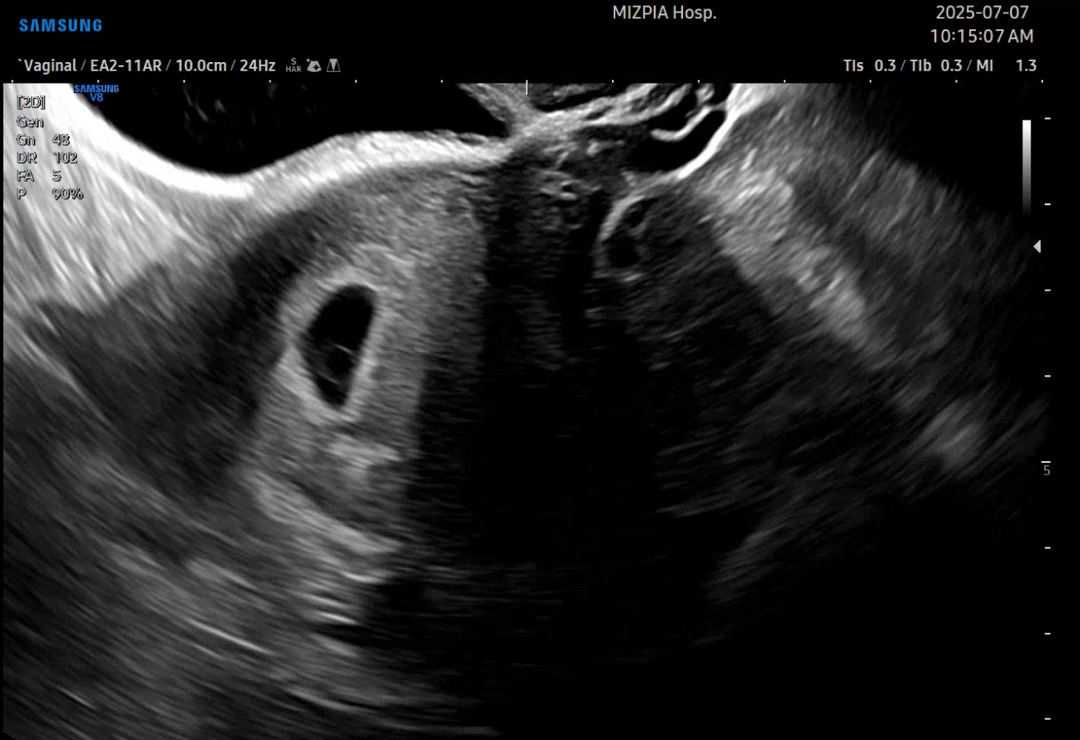

오늘 처음으로 난황 보구왔어요 원래 이 시기에는 배 초음파보단 질촘파로 확인되는거 맞져...? 처음 아기집 확인하러 갈때는 4주6일 배 초음파로 봐주시고 오늘은 난황은 배로 안보이네~ 하시고 질촘파로 다시 봤어요 난황 잘 보이나요? 5주 6일이면 저정도 흐려도 잘 만들어지고 있는거 맞나용...? 초음파 전문가님들 봐주세용

엄청 잘보여요!!!!!!

오 엄청 선명하네요!